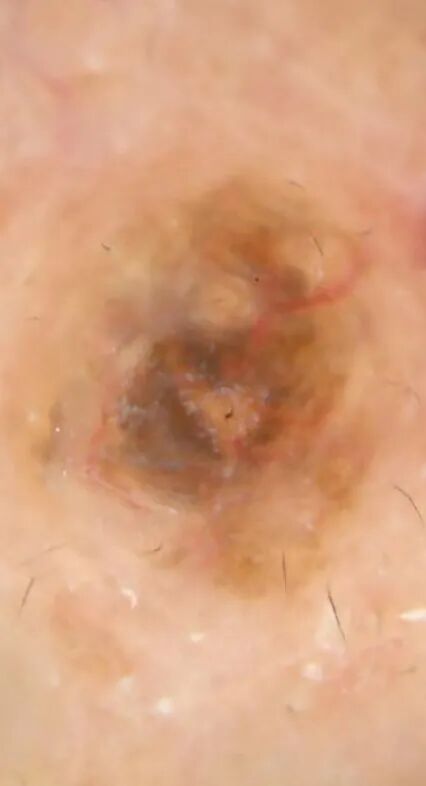

肉眼看起来这三颗痣好像没有太大区别,但在皮肤镜下,它们却有不同的表现:

左:皮内痣  中:脂溢性角化病  右:黑色素瘤